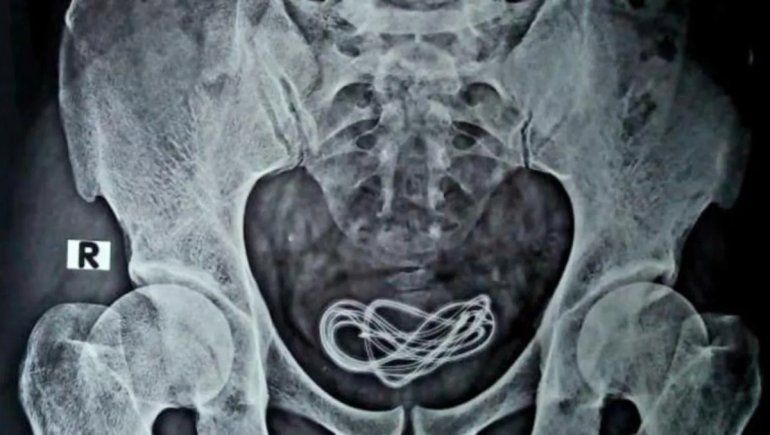

Un adolescente chino, de 13 años, debió ser operado de urgencia luego de que se metió un cable eléctrico de 70 centímetros de largo por la uretra. El joven, que tuvo el hilo metálico por más de tres meses dentro suyo, comentó que lo hizo ya que tenía curiosidad por saber de dónde proviene la orina.

El insólito hecho ocurrió en la ciudad de Dongguan, provincia de Guangdong. Tras meterse el cable, este se enredó en su vejiga y permaneció en el órgano por más de tres meses. A raíz de esto, el joven sufrió micciones frecuentes, urgentes y dolorosas, a veces incluso con sangre. En consecuencia, el chico fue trasladado a un hospital local para que le quitaran el hilo metálico mediante una cirugía.

Según el médico que lo atendió, cuando ingresó el cable eléctrico a la uretra era de color negro pero después de estar en su cuerpo durante mucho tiempo, se cubrió con suciedad de orina y se volvió grisáceo. Además, el profesional comentó que el cable habría dañado aún más la uretra y la vejiga del chico si hubiera permanecido dentro de su cuerpo.